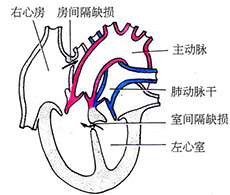

新生儿持续肺动脉高压(PPHN)

疾病介绍:新生儿持续肺动脉高压是由多种病因引起的新生儿出生后肺循环压力和阻力持续增高,而发生心内水平(通过卵圆孔)和(或)动脉导管水平的右向左或双向分流,…【详细】